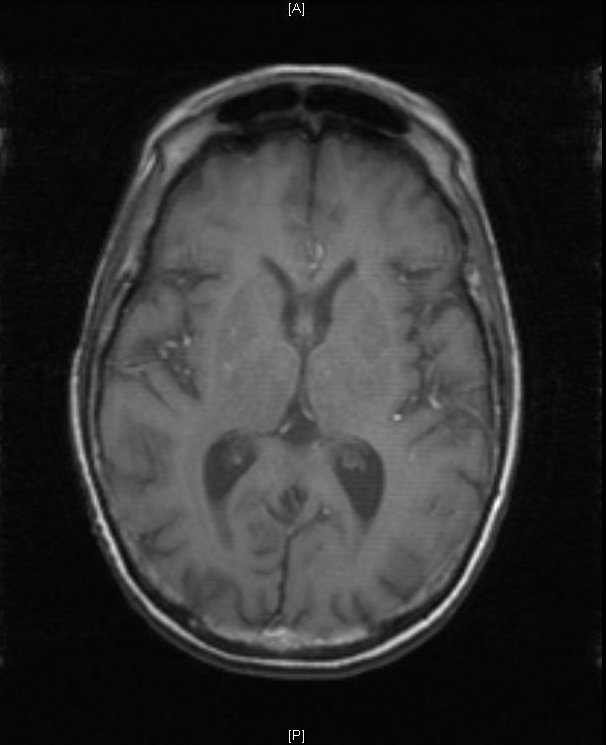

The patient had a witnessed episode of isolated left upper extremity jerking, shown in the video, during which she was completely awake and conversant. Lab results were significant for serum glucose of 1167 mg/dL, no anion gap, and negative serum/urine ketones. She had a computed tomography (CT) of the head that did not show any acute pathology, and underwent a brain magnetic resonance imaging (MRI) without any signs of stroke or other pathology, shown below.

Hyperglycemic hemichorea hemiballismus is a rare complication of hyperosmolar hyperglycemic non-ketotic syndrome (HHNS) and encompasses a range of non-patterned, involuntary movements on one side of the body.1 The pathophysiology is not fully understood, but one hypothesis suggests an increased inhibition of the subthalamic nucleus and reduction in GABA-ergic inhibition in the thalamus.2 The characteristic lesions seen on radiology include hyperdensities of the putamen, head of the caudate, and globus pallidus on CT and T1-weighted MRI contralateral to the side with symptoms, but these findings are not always seen (as in this case), nor are they specific for this disease process.3 The differential for these type of lesions also includes subacute hemorrhage, calcifications, and metal deposition.4 Most cases are benign and resolve with one to two days of normoglycemia; however, some patients can have persistent symptoms for months.2 Review of previous case reports revealed that this dyskinesia occurred more often among elderly diabetic patients but could also be an initial presentation of diabetes.5